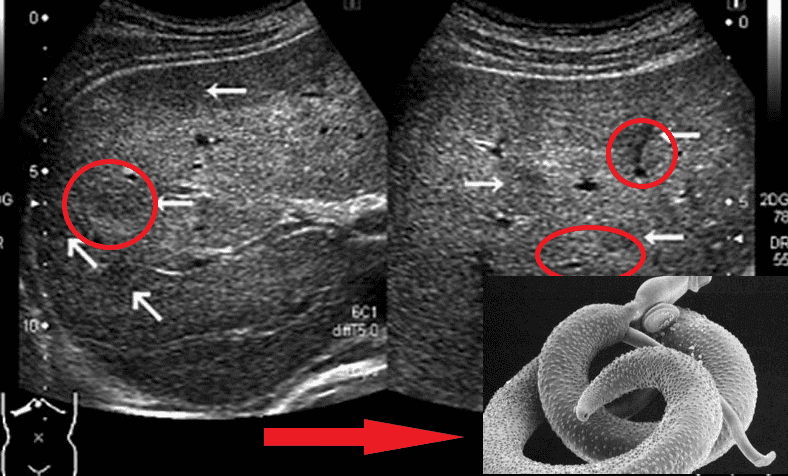

Мозок, уражений паразитами